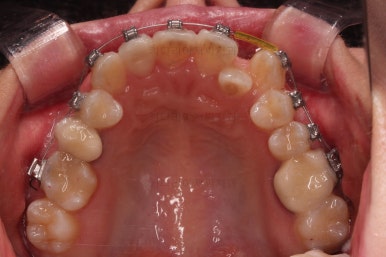

중간평가 이후 남아있는 공간은 일부 어금니를 앞으로 당겨오면서 개선하기로 했습니다.

미니스크류를 이용해 주었고요.

그래야 중심선이나 입매에 더 도움이 되기 때문이죠.

적절하게 디테일을 손보고 마무리를 합니다.

중간중간 보철된 치아도 있고, 위아래의 중앙선까지 100% 맞기는 힘든 상황이었지만 가급적이면 매우 잘 맞춰 드렸고요.

교합이라던지 가지런한 느낌도 좋네요.

우측만 위아래 뽑았지만 기능에는 문제 없이 교합을 마무리 했습니다.